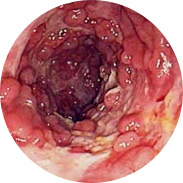

A végbél nyálkahártyájának gyulladása és felfúvódása

A vérzés vérszegénységhez vezethet

A testhőmérséklet emelkedése súlyos gyulladás mellett lázhoz vezethet

És a legrosszabb a végbélrák!A Hemoren nagyszabású klinikai vizsgálatait 2016-ban végezték el a Magyar Orvosi Központban (Budapest). Összesen több mint 1000, különböző stádiumú aranyértől szenvedő férfi és nő vett részt a vizsgálatokban. Valamennyi alany Hemoren krémet használt 3 hétig. A vizsgálat eredményei még az orvosokat is meglepték!

A férfiak több mint 95% -aés a nők 98% -anéhány napon belül jelentős javulást mutatott a Hemoren krém használatának megkezdése után, a résztvevők több mint 90% -a felépült a meglévő betegségéből. A jelenleg létező kezelési módszerek egyike sem ilyen hatékony!